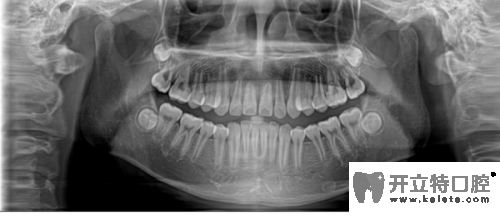

牙齒全景片

合肥崔勁松口腔正畸醫(yī)生說(shuō),矯正前做檢查是對(duì)顧客的牙齒和口腔健康負(fù)責(zé)。在做CT/全景片是能清楚的檢查到牙槽骨是否健康、有沒(méi)有牙周炎、阻生齒等情況,所以矯正治療前檢查是特別重要的。

其實(shí),正畸前的全景片檢查也是為了能更好的了解口腔情況,例如牙齒囊腫、牙根被吸收、腫瘤等,如果正畸醫(yī)生不拍這個(gè)片子,在做矯正之前就不會(huì)發(fā)現(xiàn)這些情況,那就是屬于很不負(fù)責(zé)的做法。全景片還可以的測(cè)定牙齒傾斜角度、牙根情況、牙槽骨質(zhì)情況、牙周軟組織情況,解剖牙齒形態(tài)的測(cè)量,能讓醫(yī)生在矯正前依靠全景圖像更精準(zhǔn)的分析、設(shè)計(jì)治療方案。